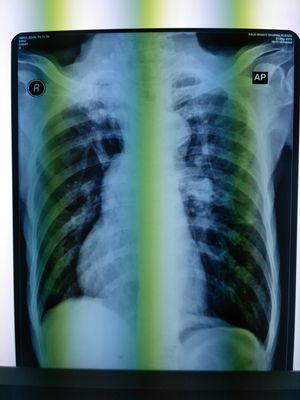

Thorax X-ray PA

What is your dx?

Dextrocardia

dextrocardia with fibrosis

Right apical fibrosis with upward diversion of vessels.